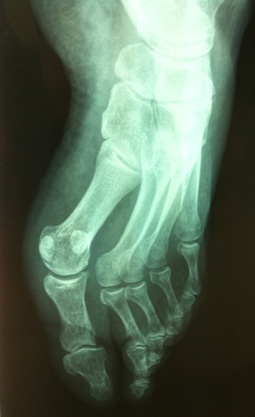

Mme H., née en 1943, sans antécédent particulier, a présenté une douleur de l’avant-pied gauche, apparue après une marche habituelle de quelques kilomètres. Elle présente un gonflement local et une douleur exquise à la palpation des 2ème et 3ème rayons.

Une radiographie est demandée (ci-dessous) et revient normale.